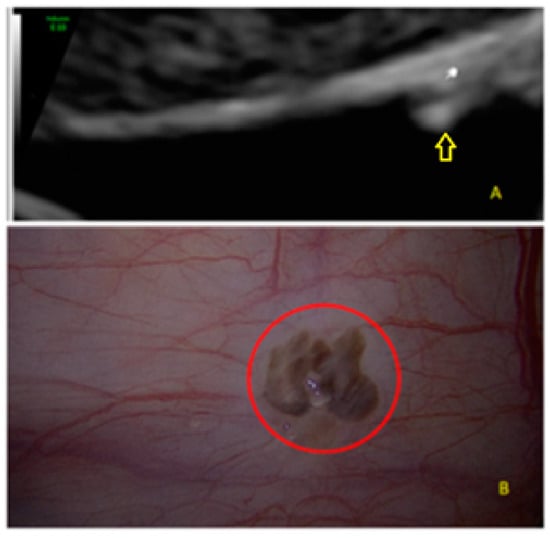

- The lesion may be convex, protruding from the peritoneal surface into the peritoneal cavity (we called this “bulging”), or it may appear as a concave defect in the peritoneum (we called this a “pocket”).